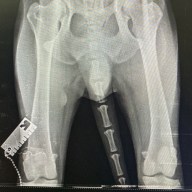

Мы выполняем хирургические манипуляции любого уровня сложности .